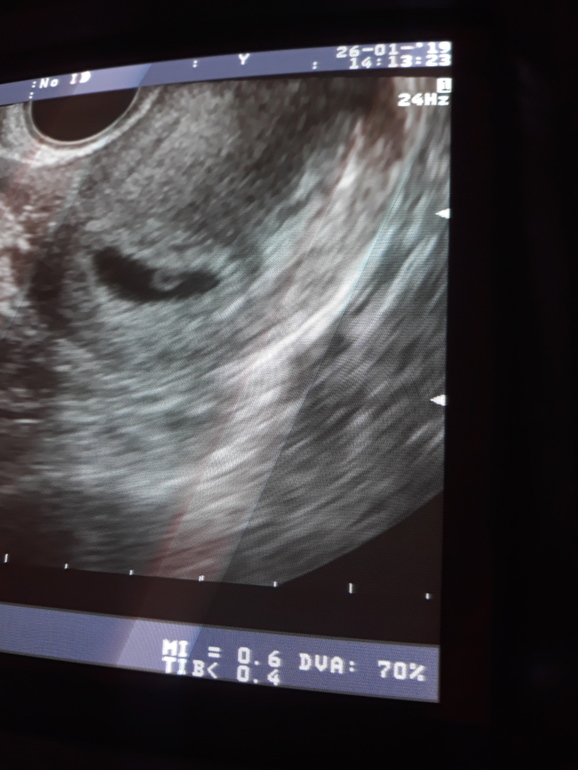

вот фото ровно через неделю после этого узи

Вопросы про УЗИ, обследования и анализы: что, где, как, когда?подскажите пожалуйста, была на узи ровно 6 акушерских недель пя 10мм эмбриона не увидели сказали вроде из за гипертонуса, врач написала беременность малого срока. подскажите у кого в таком сроке не увидели эмбриона очень переживаю и пя какому сроку примерно соответствует?

Вот это точно! Я не выдержала пошла в платную клинику и плодное яйцо ровно за неделю выросло 21мм эмбрион уже 5мм и сердцебиения уже есть) даже размеры матки совсем не соответствуют когбудто уменьшились. Срок поставили 5 недель) так что лучше заплатить и сделать нормальное узи!